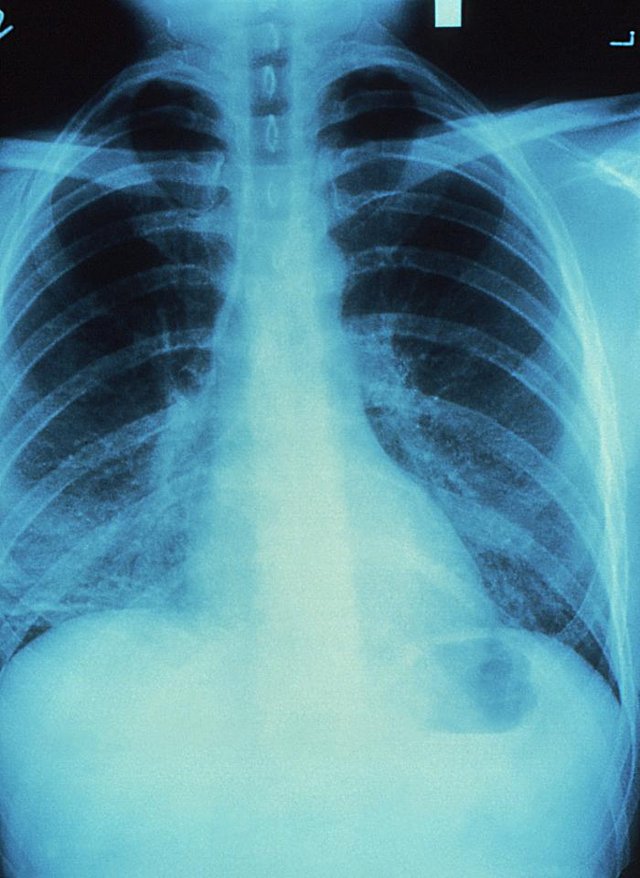

Bildgebung

© CDC/ Jonathan W.M. Gold. M.D.

© CDC/ Dr. Thomas Hooten

Bildgebung:

Standarduntersuchung bei Verdacht auf Pneumonie ist die Röntgenthoraxaufnahme:

• Nachweis eines neu aufgetretenen Infiltrats

• Erfassen von Befundausdehnung

• Erfassen von Begleiterkrankungen (z.B. Herzinsuffizienz) und Komplikationen (Pleuraerguss, Lungenabszess)

• Hilfestellung bei differenzialdiagnostischen Überlegungen